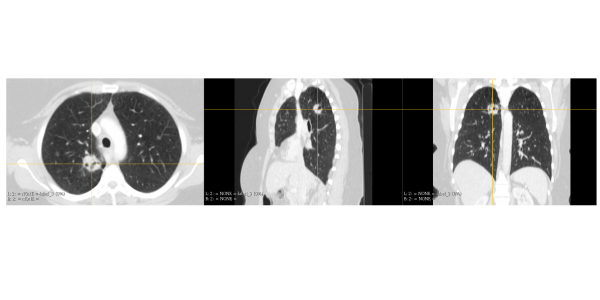

Comprised of a team of Biomedical Engineers, we are experienced in medical terminology and imagery.

TRINOTA aims to help doctors assess patient specific treatment efficacy with the use of 3D visualization (Physical and Digital Models) of a patient's region of interest (ROI).

With the use of our Ultra High Resolution Professional Grade 3D Printer, we can produce physical models of the patient's ROI.